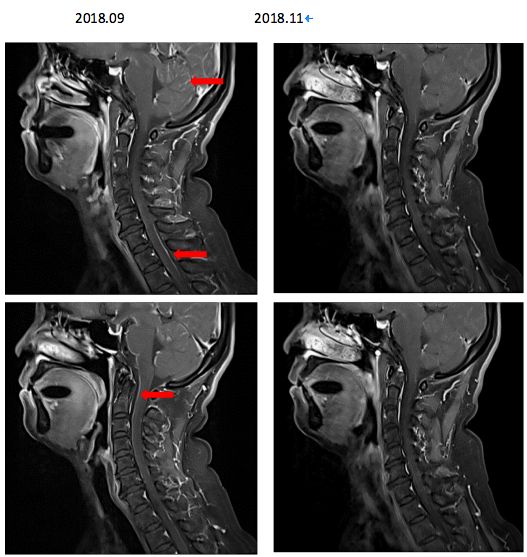

患者于2018年9月27日因“剧烈头痛伴呕吐”就诊于我科——郑州大学附属第一医院肿瘤科,查体急性病容,表情痛苦,神志清楚,脑膜刺激征可疑阳性,考虑脑膜转移性可能性大,故立即行腰椎穿刺,提示颅内压400mmH2O,并行脑脊液细胞学检查 ,未见肿瘤细胞。但是结合患者症状体征仍不能排除脑膜转移可能。故行颈椎增强MRI排除其他部位脑脊液转移可能,检查结果提示颈椎增强MRI可见脑脊膜多发转移(图6)。

图6. 颈椎增强MRI提示脑脊膜多发转移影像

2018年9月29日,患者病情出现恶化,出现头痛伴短暂性意识障碍,查体双侧瞳孔等大等圆,对光反射灵敏,心率45次/分,血压160/100mmHg,考虑颅内高压导致出现Cushing反应。立即予以镇静、脱水等对症处理,并紧急腰穿行脑脊液引流,同时鞘内注射培美曲塞化疗联合全身培美曲塞单药化疗。患者于2018年9月30日恢复意识,并能交流顺畅,活动自如。同日,患者开始口服靶向阿来替尼二线治疗,并于10月2日因头痛再次腔内注射培美曲塞单药化疗。后患者肺部和中枢神经系统控制可,患者PS评分恢复0分。从治疗的结局来看,该病例算是一例非常成功的脑膜转移治疗成功的病例。

图7.治疗后复查患者颈椎核磁影像